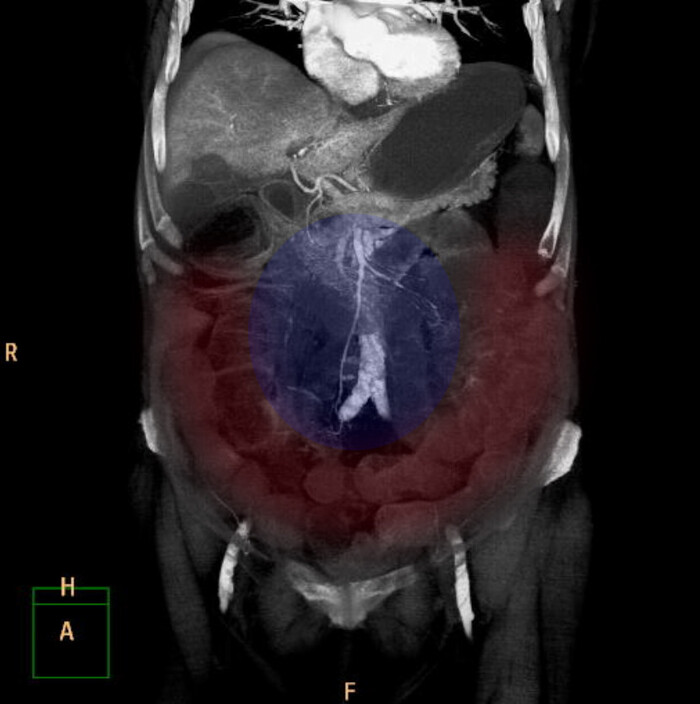

По КТ в мягкотканном окне (специальные настройки яркости и контраста для лучшего отображения мягких тканей) определялись увеличенные лимфатические узлы в средостении справа паратрахеально, в области корня правого лёгкого и инфракаринально (ниже места "разделения" трахеи на правый и левый бронх):

1 и 2: аксиальные срезы, 3 - корональная реконструкция; лмф.узлы - красные стрелки